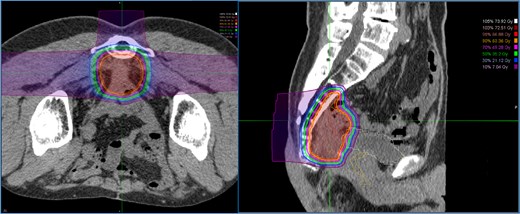

A 52-year-old man underwent emergency Hartmann’s procedure for peritonitis caused by perforated sigmoid colon cancer. The tumor was staged as pT4b N0 M0 with no lymphovascular invasion. Postoperative examination revealed synchronous advanced lower rectal cancer. Systemic chemotherapy with mFOLFOX6 plus bevacizumab was administered, followed by neoadjuvant chemoradiotherapy and abdominoperineal resection. Pathological examination confirmed pT3 N0 M0 disease, with no lymphovascular invasion. A total of 2 years and 4 months after the initial surgery, a solitary lung metastasis appeared and was surgically resected. Three years after the initial surgery, imaging revealed LRRC on the anterior surface of the sacrum (Fig. 1). Given the history of multiple laparotomies and treatment for distant metastases, surgical resection was considered inappropriate. After thorough consultation with a CIRT facility and the patient, a plan was made to perform CIRT followed by prophylactic resection of the adjacent irradiated small intestine that was thought to be at a high risk of causing ulcers and perforation. CIRT was administered using carbon ion beams at a dose of 70.4 Gy (relative biological effectiveness weighted dose) in 16 fractions over 4 weeks (Fig. 2). Three months after completion of CIRT, the irradiated small intestine, including a 30-cm segment adherent to the recurrent site, was prophylactically resected (Fig. 3A and B). The serosal surface appeared intact (Fig. 3C), and observation using indocyanine green (ICG) fluorescence imaging indicated good blood flow (Fig. 3D). However, the mucosal surface showed ulcer formation near the adhesion site (Fig. 4). Histopathologically, the ulcerated areas showed necrosis at the ulcer base surface and transmural infiltration of inflammatory cells (Fig. 5). The postoperative course was uneventful, and the patient has remained recurrence-free for 2.5 years.

Dose distribution for carbon ion radiotherapy. The irradiation field includes the recurrent lesion, the anterior surface of the sacrum, and the adjacent small intestine.